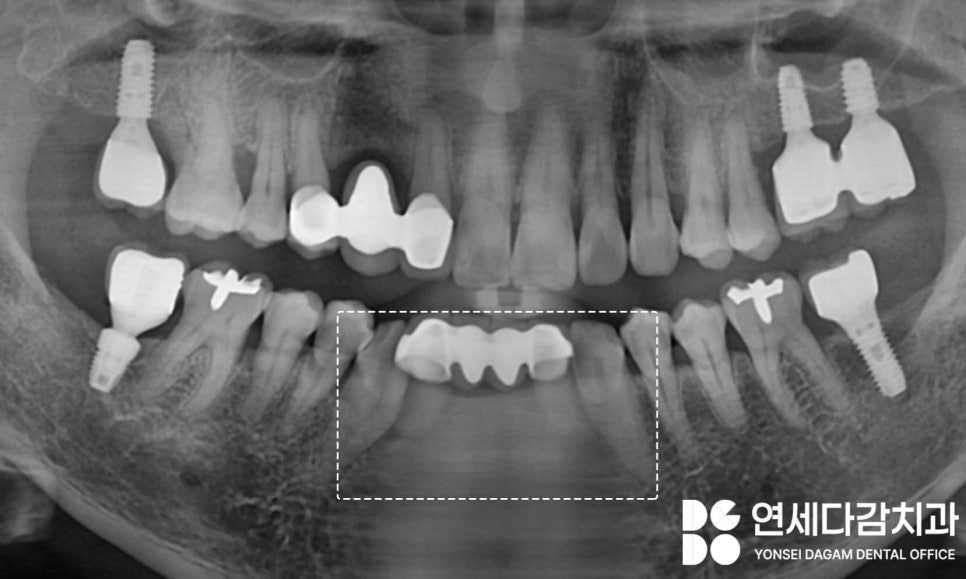

위 엑스레이 사진을 살펴보면

아래 앞니에

브릿지(Bridge) 형태의 보철을

착용하고 있는 것을 확인할 수 있습니다.

지대치 역할을 하고 있는

치아 뿌리 주변의 뼈가 손상되어

있는 상태입니다.